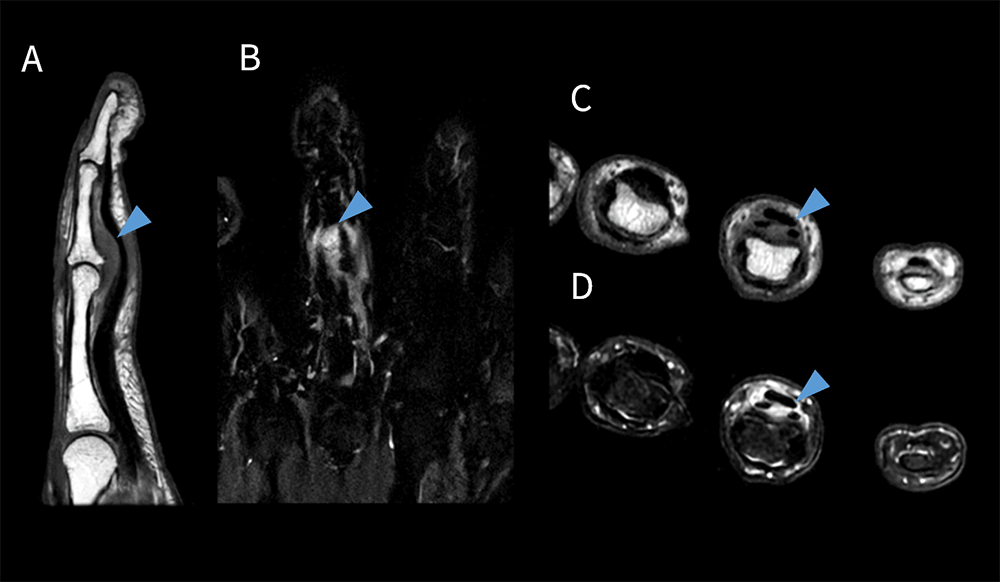

Prime_Tamaki_08.png

図6 脳梗塞患者におけるVolume DWI

A. Volume DWI Axial、B. Coronal Reformat、C. Sagittal Reformat

スライス厚:2.2mm 撮像時間:2:40 min

Volume DWI は通常のDWI(Conventional DWI)よりもスライス厚が薄いため、微小脳梗塞の検出に優れ、MPR処理することにより他方向からの観察も容易となる一方で、SNRが低下しやすいデメリットがある。従来はSNRを担保するためには加算回数を増やす必要があり、予約時間枠外での撮像を余儀なくされていたが、AIR™ Recon DLによってConventional DWIと遜色ないSNRのVolume DWIを3分以内で撮像することが可能となり、予約検査時間内での追加撮像を可能としている。